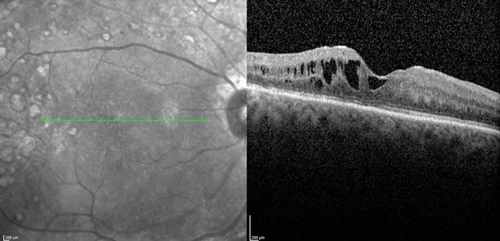

The clinical efficacy and safety of the drug have been also reported in two case reports of vitrectomised eyes with persistent DMO with both cases showing a desirable anatomical outcome. In one case, the authors have suggested that vitrectomy seemed to have enhanced the performance of the implant in-situ and achieved complete DMO resolution [19]. In a recently presented series of 20 post PPV eyes of 18 patients treated with Iluvien, a mean change of BCVA of +9 ETDRS letters (range -6 to +27) as well as mean reduction of CRT by -224µm (-595 to +126) were reported after a mean follow-up period of 201 days (range: 45 to 367 days) (SFO Paris 2016). Further real-life data of Iluvien in vitrectomised eyes with comparable clinical outcomes are awaited with interest. The author’s experience with the drug so far is in-keeping with published cases (Figure 1).

Figure 1 (a).

Figure 1: Case study for management of post-vitrectomy refractory DMO: (a) Pre-vitrectomy; (b) Post-vitrectomy; (c) Post six intravitreal anti-VEGF treatment with sub-optimal response; (d) Post-Iluvien one month. Complete resolution of DMO; (e) Post-Iluvien 10 months. Maintained response to treatment. (Courtesy of Mr David H W Steel - Sunderland Eye Infirmary).